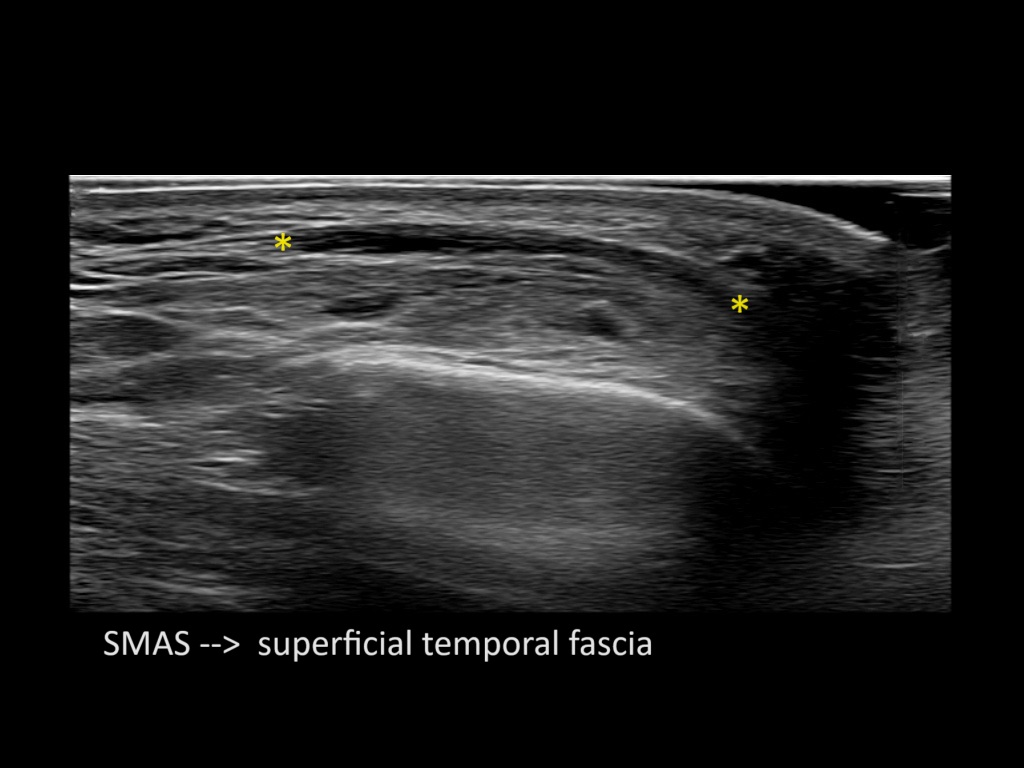

Filler behavior - Temple zygoma US

Study the first image to recognize the different layers. If you are sure about the layers, swipe to the second image to view the answer (if applicable).